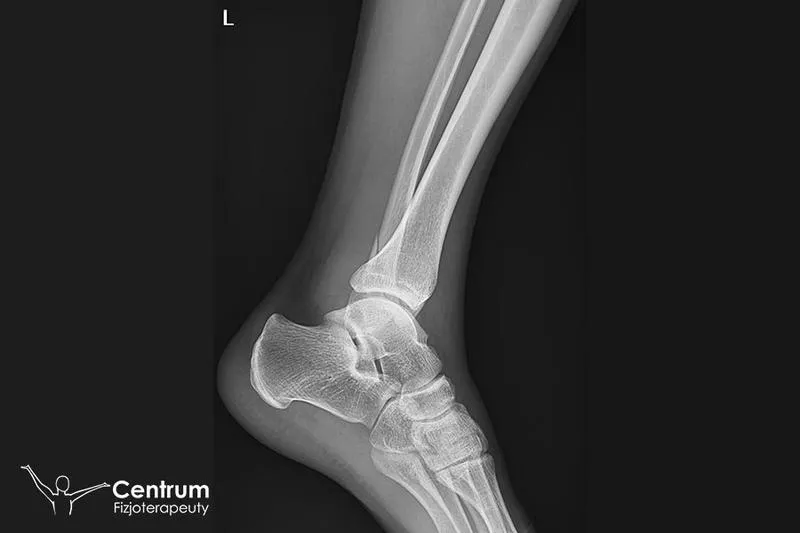

Złamanie kostki to uraz, który skutecznie wyłącza nas z codziennych działań. Aby powrócić do pełnej sprawności, konieczne staje się zaangażowanie w rehabilitację. Proces rehabilitacji dzieli się na kilka właściwych etapów, które zazwyczaj rozpoczynamy po zdjęciu gipsu lub ortezy. To właśnie rehabilitacja odgrywa kluczową rolę w odzyskiwaniu pełnej funkcji stawu. W większości przypadków rehabilitacja trwa od trzech do sześciu miesięcy, ale warto pamiętać, że indywidualne predyspozycje pacjenta oraz charakter złamania znacząco wpływają na tempo tego procesu.

Rehabilitacja po złamaniu kostki pełni kluczową rolę w przywracaniu pełnej sprawności. Ten powszechny uraz potrafi na dłuższy czas wyłączyć nas z codziennych aktywności, dlatego ważne jest, aby podejść do rehabilitacji z odpowiednią starannością. Właściwe działania rehabilitacyjne nie tylko pozwalają na szybkie odzyskanie mobilności, ale również minimalizują ryzyko powikłań, które mogą negatywnie wpływać na życie przez wiele lat. Warto zrozumieć, że rehabilitacja stanowi całościowy proces regeneracyjny, a nie tylko zbiór ćwiczeń.

Powrót do pełnej sprawności wiąże się z systematycznością oraz umiarkowanym tempem działania. Po usunięciu gipsu lub ortezy, rehabilitacja skupia się na zmniejszeniu bólu, redukcji obrzęku oraz poprawie mobilności stawu skokowego. Wprowadzenie odpowiednich ćwiczeń jest kluczowe, ponieważ ich brak prowadzi do osłabienia mięśni. To z kolei może skutkować chroniczną niestabilnością stawu i przewlekłymi dolegliwościami bólowymi. Dlatego współpraca z fizjoterapeutą okazuje się niezbędna, gdyż jego wiedza i doświadczenie umożliwiają dostosowanie rehabilitacji do indywidualnych potrzeb pacjenta.